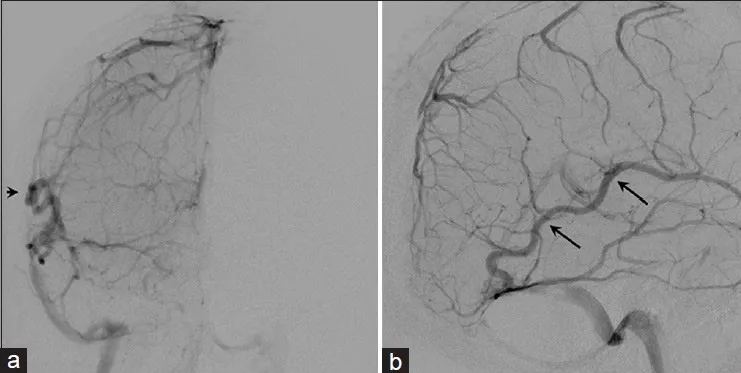

术前治疗方案包括对颈外动脉的肿瘤供血动脉进行栓塞处理,主要栓塞对象为枕动脉和脑膜中动脉分支,使用弹簧圈及聚乙烯醇颗粒作为栓塞材料。初步病理检查通过小切口切开活检实施,病理分析确认为世界卫生组织(WHO)I级脑膜瘤。

术前充分评估静脉引流途径,明确Labbe静脉的皮质静脉侧支引流和枕窦的深部结构静脉侧支引流